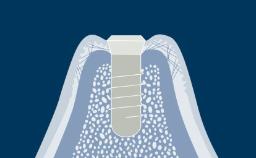

O momento em que os implantes são colocados em função é marcado pela conexão da prótese ao implante. A escolha do protocolo de carregamento mais adequado é um passo importante no processo de planejamento do tratamento. Ao selecionar o momento da reabilitação com implante, você se depara com uma importante decisão clínica. Este módulo apresenta os diferentes critérios para escolher os protocolos de carregamento.

- listar as definições de protocolos de carregamento de implantes imediatos, precoces e convencionais